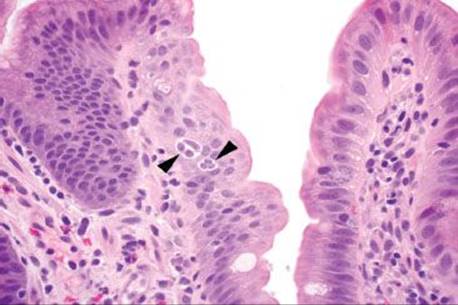

Figure 3.315 Sneaky adenocarcinoma involving the duodenal mucosa. Under oil immersion, note the nuclear irregularities, abundant pink cytoplasm, and cytoplasmic mucin droplet (arrowhead) characteristic of pancreatobiliary adenocarcinoma. Unfortunately, sometimes 38 levels are required for the ultimate diagnosis and sometimes only a few malignant cells are present! When the clinical scenario and the histology are not aligned, deeper sections (and deeper sections and deeper sections and deeper sections) are often required.

This case was received as “prominent ampulla, concerning for malignancy” (Fig. 3.313). The initial sections show duodenal mucosa with acute and chronic inflammation, gastric foveolar metaplasia, and marked reactive epithelial change (Fig. 3.313). Although these histologic features can account for a nodular clinical impression, deeper sections were pursued based on the clinical suspicion for malignancy. The first set of deeper sections were similarly concerning, but definitive malignancy was not seen. Deeper sections were repeated. And repeated. And repeated. In this case, the tissue block was exhausted and on the 38th level (!!!), clear lymphovascular invasion and infiltrating adenocarcinoma were seen (Figs. 3.314 and 3.315). When the histology does not fit the clinical scenario, consider deeper sections. When the deeper sections are not conclusive, consider repeat deeper sections or recommend rebiopsy (in this case, the patient was too unstable for a subsequent biopsy).